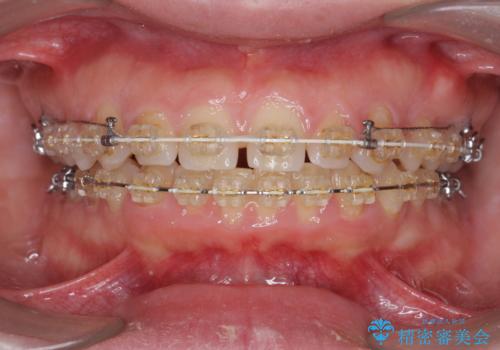

深い噛み合わせ、すきっ歯の改善 ワイヤーを用いたマルチブラケット矯正

- 噛み合わせが深く、前歯が突き出て隙間が出てきたことの改善を希望され矯正治療の相談で当院に初診来院されました。

ワイヤーを用いたマルチブラケット矯正を行うことで深い噛み合わせを改善し、前歯の隙間もなくし審美的な歯列へと治療をおこなっていきます。